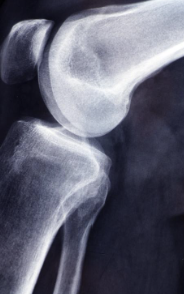

글루코사민 콘드로이친 msm 효능 및 부작용 적정섭취량 등 관련 정보 알아보도록 하겠습니다. 관절은 뼈와 뼈 사이에 위치한 연결점으로, 우리 몸을 움직이기 위한 중요한 부분입니다. 관절은 뼈의 끝에 위치한 연골과 뼈를 연결하는 인대로 이루어져 있으며, 이러한 구조는 원활한 움직임을 가능하게 합니다. 하지만 연령이 들어가거나 부상 등으로 인해 관절의 기능이 손상되면 관절염과 같은 질환으로 발생할 수 있습니다. 이러한 질환은 관절 통증, 감각 이상, 염증 및 손상 등을 일으키며, 일상생활에서의 움직임과 활동에 지장을 주어 생활의 질을 저하시킵니다. 이에 따라 적절한 치료와 예방이 필요하며, 영양소와 운동 등을 통한 관리가 중요합니다.